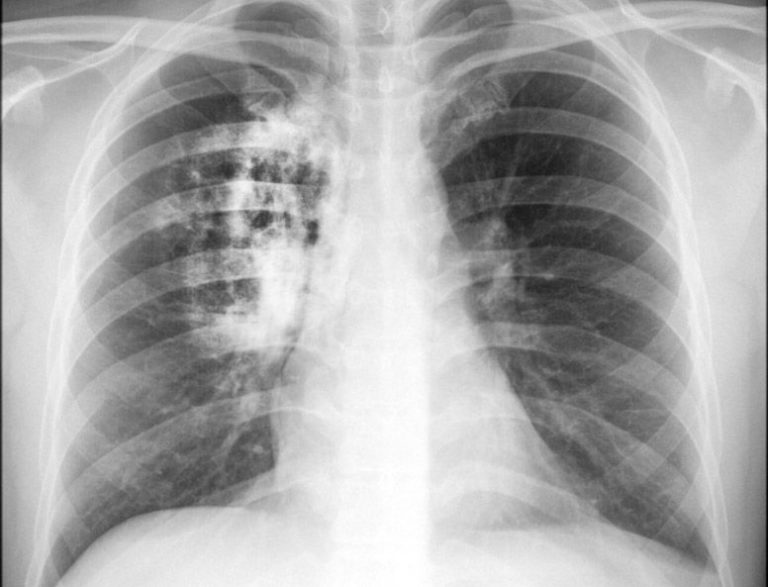

Exame de rastreamento é feito com grupo de risco que são fumantes de 55 anos; nesta quinta-feira (1º) é o...